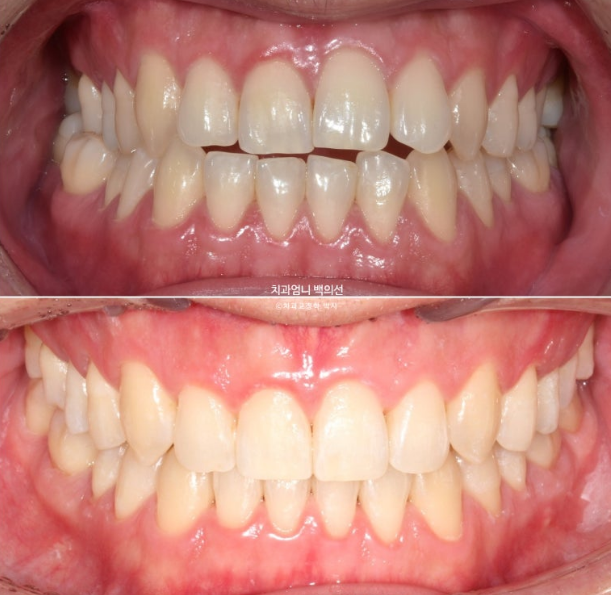

This is a story about Invisalign treatment with palatal expansion for a patient with a Class III bite and facial asymmetry.

This patient visited us in December 2022 to correct anterior crossbite and open bite.

The blue arrow indicates that the molar bites in reverse.

This is called a crossbite.

Because the lower arch is wider than the upper arch, this is a crossbite.

In addition, due to the underbite, crossbite is also seen in the canines and front teeth.

A mandibular asymmetry with the lower jaw shifted to the right is also visible, along with an open bite where the upper and lower teeth do not meet.